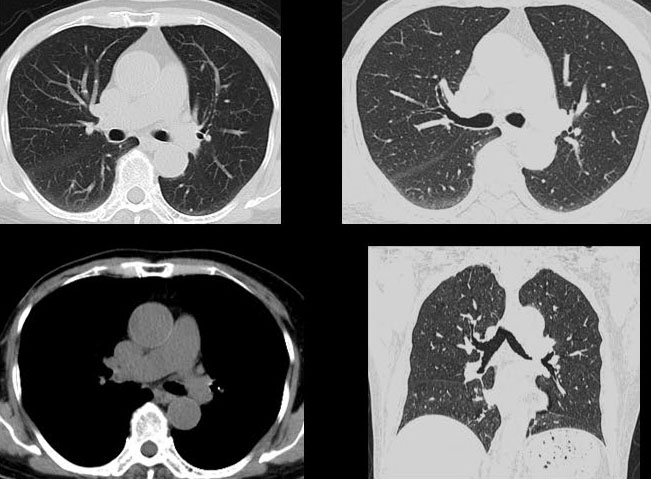

体 检

具备业内最先进的低剂量技术,60千伏精控球管技术。辐射剂量小,是健康体检最优选择。

联影ct怎么样【小南快讯】辐射低、成像快、更精确!CT届的“天花板”——320排640层超高端CT落户奉中心!_https://www.jmylbn.com_新闻资讯_第17张